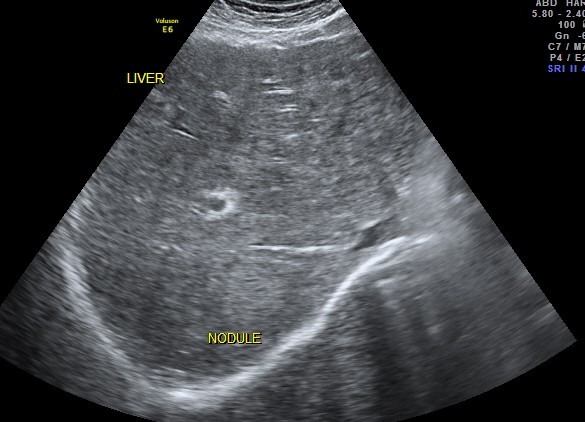

This 74 year old gentleman has been coming to me for more than 10 years for mild systemic hypertension and hypothyroidism.He used to smoke cigars until a few years ago. 3 years ago he developed unexplained giddiness and on evaluation was found to have pituitary macroadenoma. Endocrine and neuro surgical consulatations were sought and he was on cabergoline and was doing very well. In April 2012 , he came for a routine review and was asked to continue his existing medications . One week later he came again with severe right upper quadrant pain and aversion to food. There was no history of cough in the recent past. He was advised an ultrasound scan of the abdomen and the findings are as below.

CT scan of the abdomen confirmed the findings ; For further clarification PET whole body scan was done at a centre in Chennai. The following images are from that.